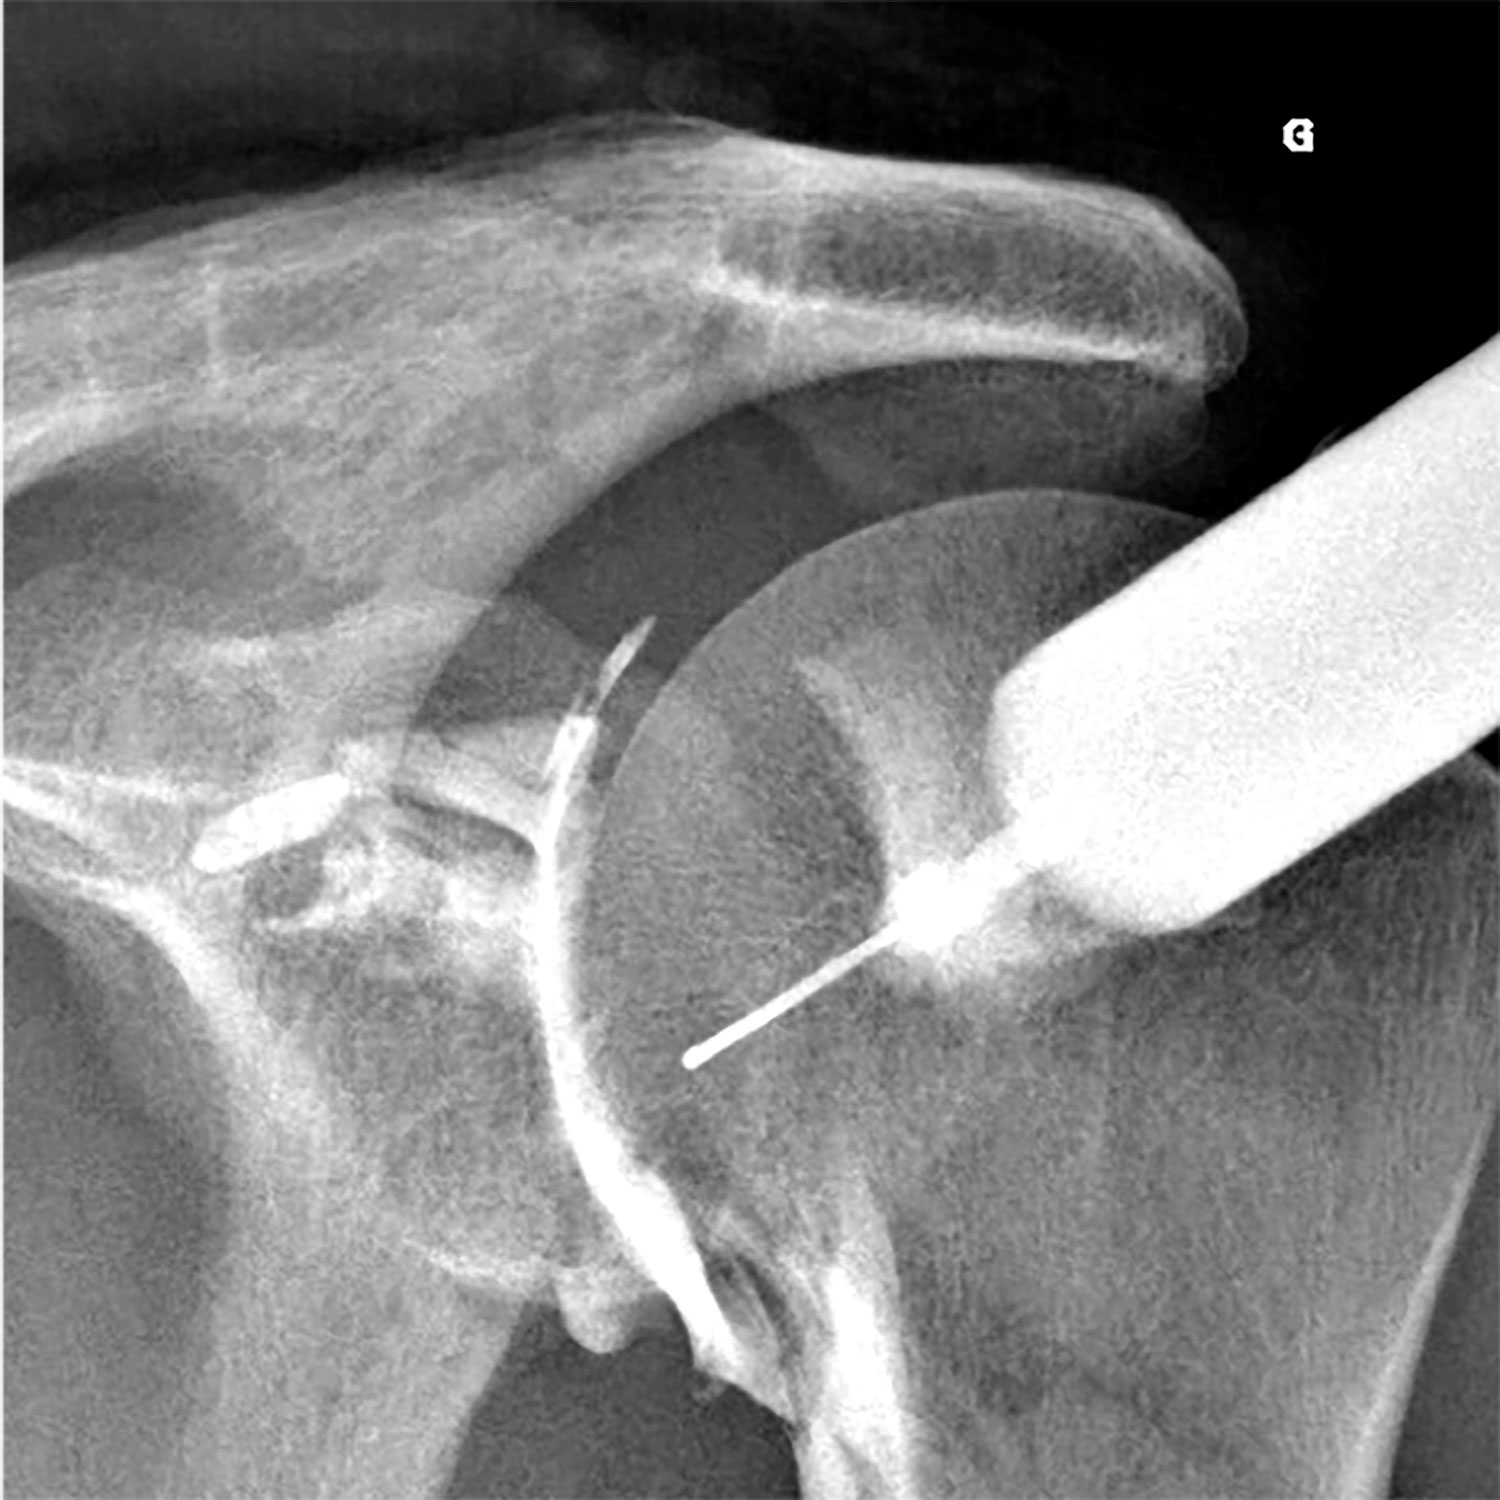

Les infiltrations radioguidées (infiltrations sous radioscopie)

Un grand nombre d'infiltrations s'effectuent sous guidage radioscopique. Pour ces gestes, il est souvent nécessaire d'utiliser un produit de contraste iodé pour vérifier la bonne injection du produit anti-inflammatoire au niveau de la zone souhaitée. Ces infiltrations concernent souvent la colonne vertébrale, mais également les articulations périphériques (épaule, coude, poignet, main, hanche, genou, cheville, pied...).